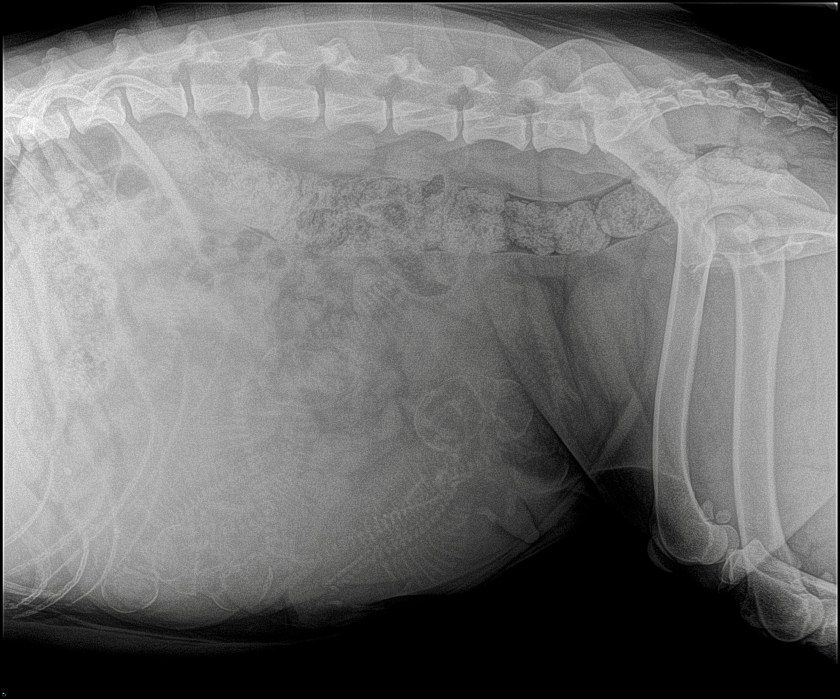

10 January – Day 52

How many puppies can you see? 8? 9? 10?

We’ve been thinking about you Poppy! I’m sure I can count at least nine skulls and spines. I was one short in my count last pregnancy so perhaps she’ll have 10 this time.